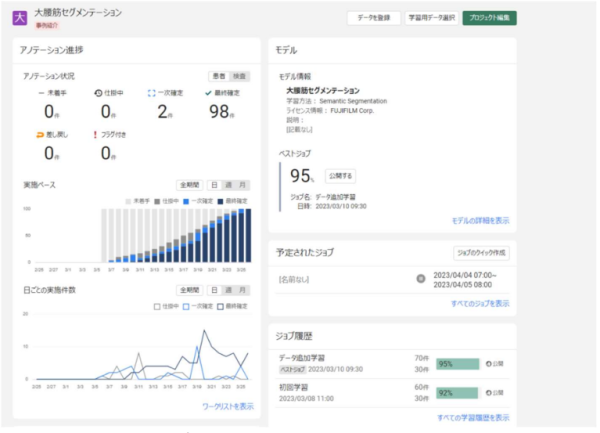

・ 複数の研究者が並行してアノテーションを行うことを想定した「プロジェクト管理ツール」を搭載。開発プロジェクトチームで大量の正解データを効率的に加工することをサポートする。

(3) 「ユーザーポータル・ダッシュボード」で活用状況をモニター可能

・ データベース上に登録された大量の医用画像や、所見などを含むレポート情報がどのように活用されているかを管理画面上でモニターできる。 J-MID を利用する各施設からアップロードされた画像やレポート情報のデータ容量や、ダウンロードされた容量を参照し、各施設での活用状況を把握することができる。